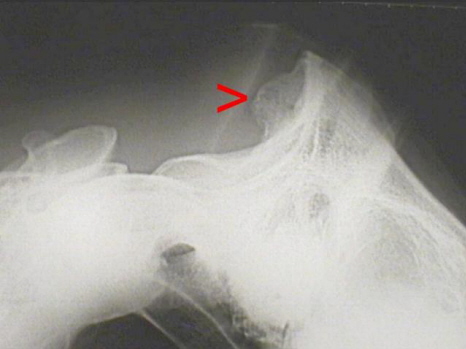

Insertionsdemopathie Genick